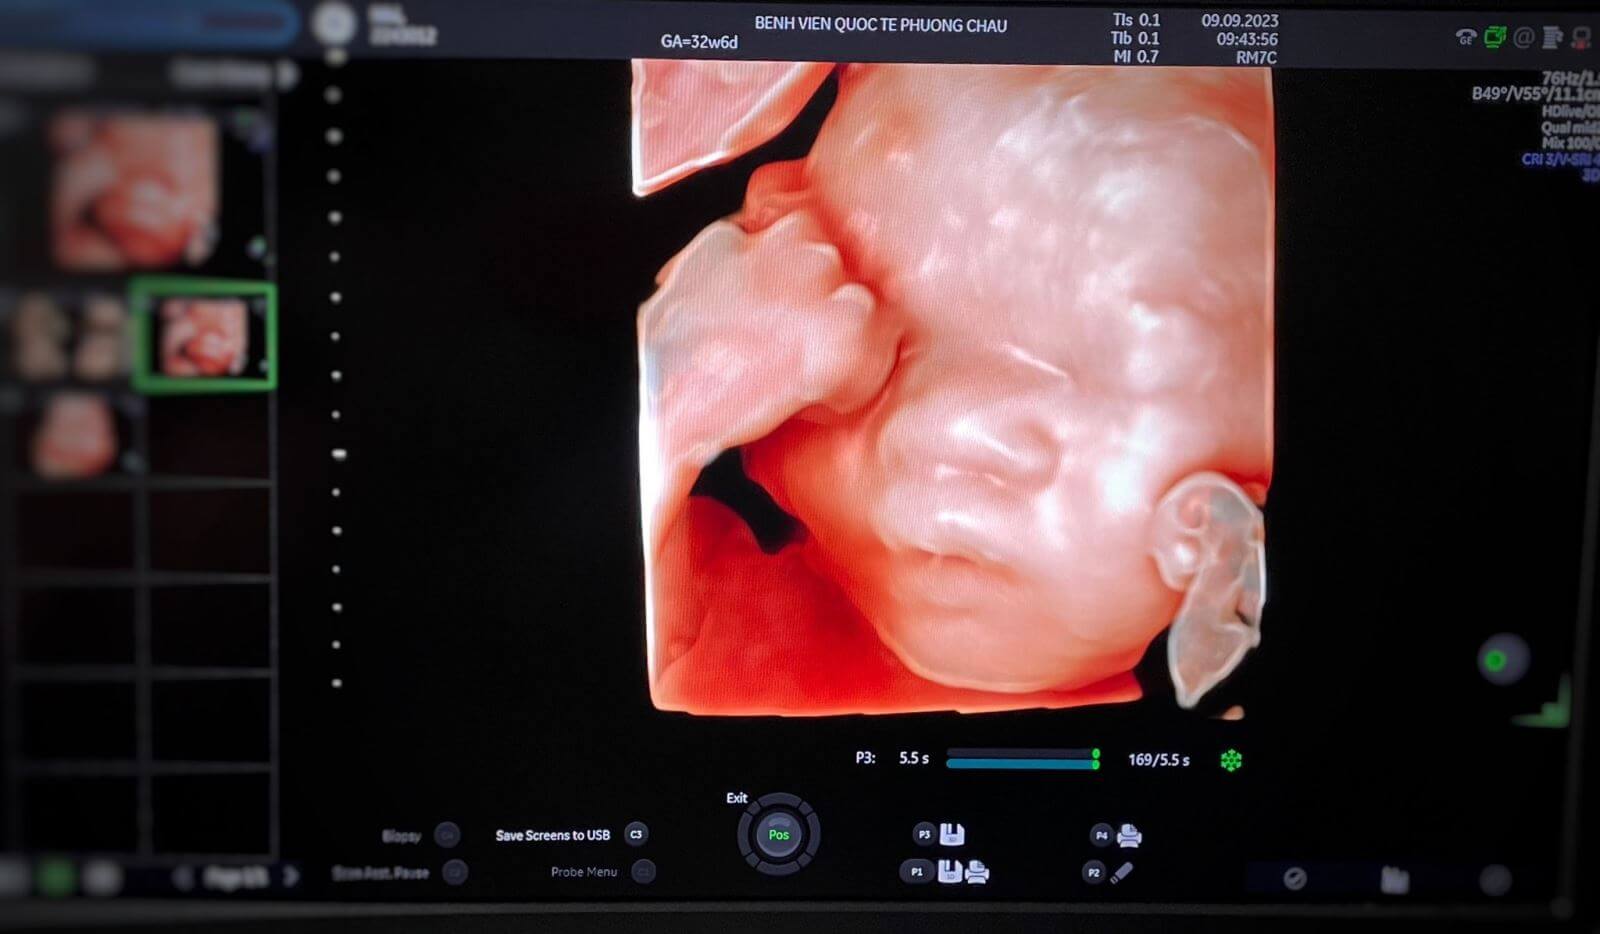

Với mong muốn mang đến cho quý khách hàng những trải nghiệm khám chữa bệnh thoải mái và hài lòng nhất, Phương Châu không chỉ sở hữu đội ngũ y bác sĩ giàu kinh nghiệm mà còn trang bị các máy móc, trang thiết bị hiện đại hàng đầu thế giới để hỗ trợ cho công tác khám chữa bệnh trở nên hoàn thiện hơn. Hiện nay, BVQT Phương Châu đã sở hữu máy siêu âm Voluson Expert 22 (E22) được mệnh danh là “Cuộc cách mạng hình ảnh học trong siêu âm Sản Phụ Khoa”. Với các tính năng ưu việt chưa từng có trong các thiết bị siêu âm trước đây, loại máy này chính là trợ thủ đắc lực giúp cho các bác sĩ xem được những hình ảnh chân thực, chất lượng cao về các vấn đề trong siêu âm sản khoa và phụ khoa.